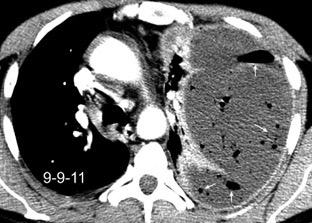

Absceso secundario a perforación de carcinoma. 3-4%. En flexura esplénica puede tener absceso subfrénico o empiema.

Empiema pleural secundario a carcinoma de la flexura esplénica (masa visible)

Lian R et al. Empyema caused by a colopleural fistula. Medicine (Baltimore) 2017/Osada T,, et al. Thoracic empyema associated with recurrent colon cancer: report of a case and review of the literature. Dis Colon Rectum 2001